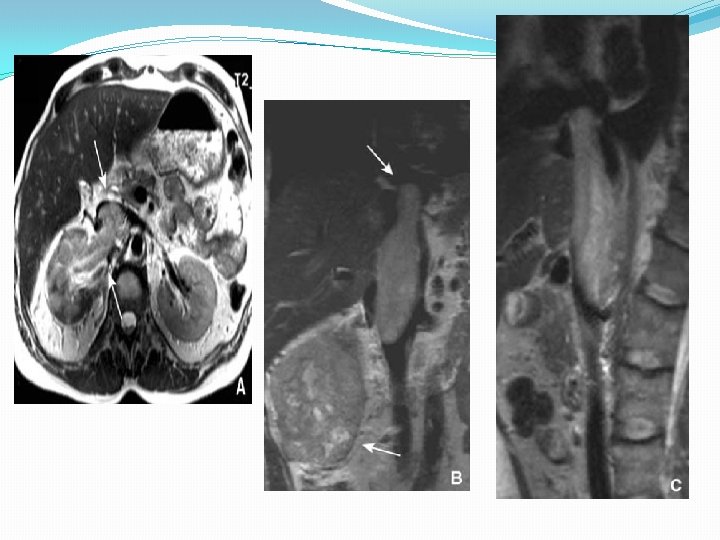

Imagerie par résonance magnétique �Les critères sémiologiques sont voisins de ceux de la TDM �L’IRM permet de mieux caractériser les lésions de petites dimensions • N’induit pas d’irradiation �La sensibilité : 90 %

Carcinome rénal atypique Tumeur de petite taille Carcinome solide hypovasculaire IRM supérieure au scanner Carcinomes multiples bilatéraux Possibilité de métastases ou de lymphome Carcinomes infiltrants Carcinome à composante graisseuse Exceptionnel, possibilité d’angiomyolipome bénin

Extension locorégionale: évalue de façon identique par la TDM et l’IRM Extension lymphatique: sensibilité comparable TDM/IRM 90% > 1, 5 cm suspecte > 2 cm métastatique Forme arrondie plutôt qu’ovalaire

Extension veineuse: TDM: sensibilité 85% Changement de forme Augmentation du diammètre IRM: sensibilité 80% VR 100% VCI Nature du thrombus (néoplasique ou cruorique) Examen de choix pour précisé la limite supérieur